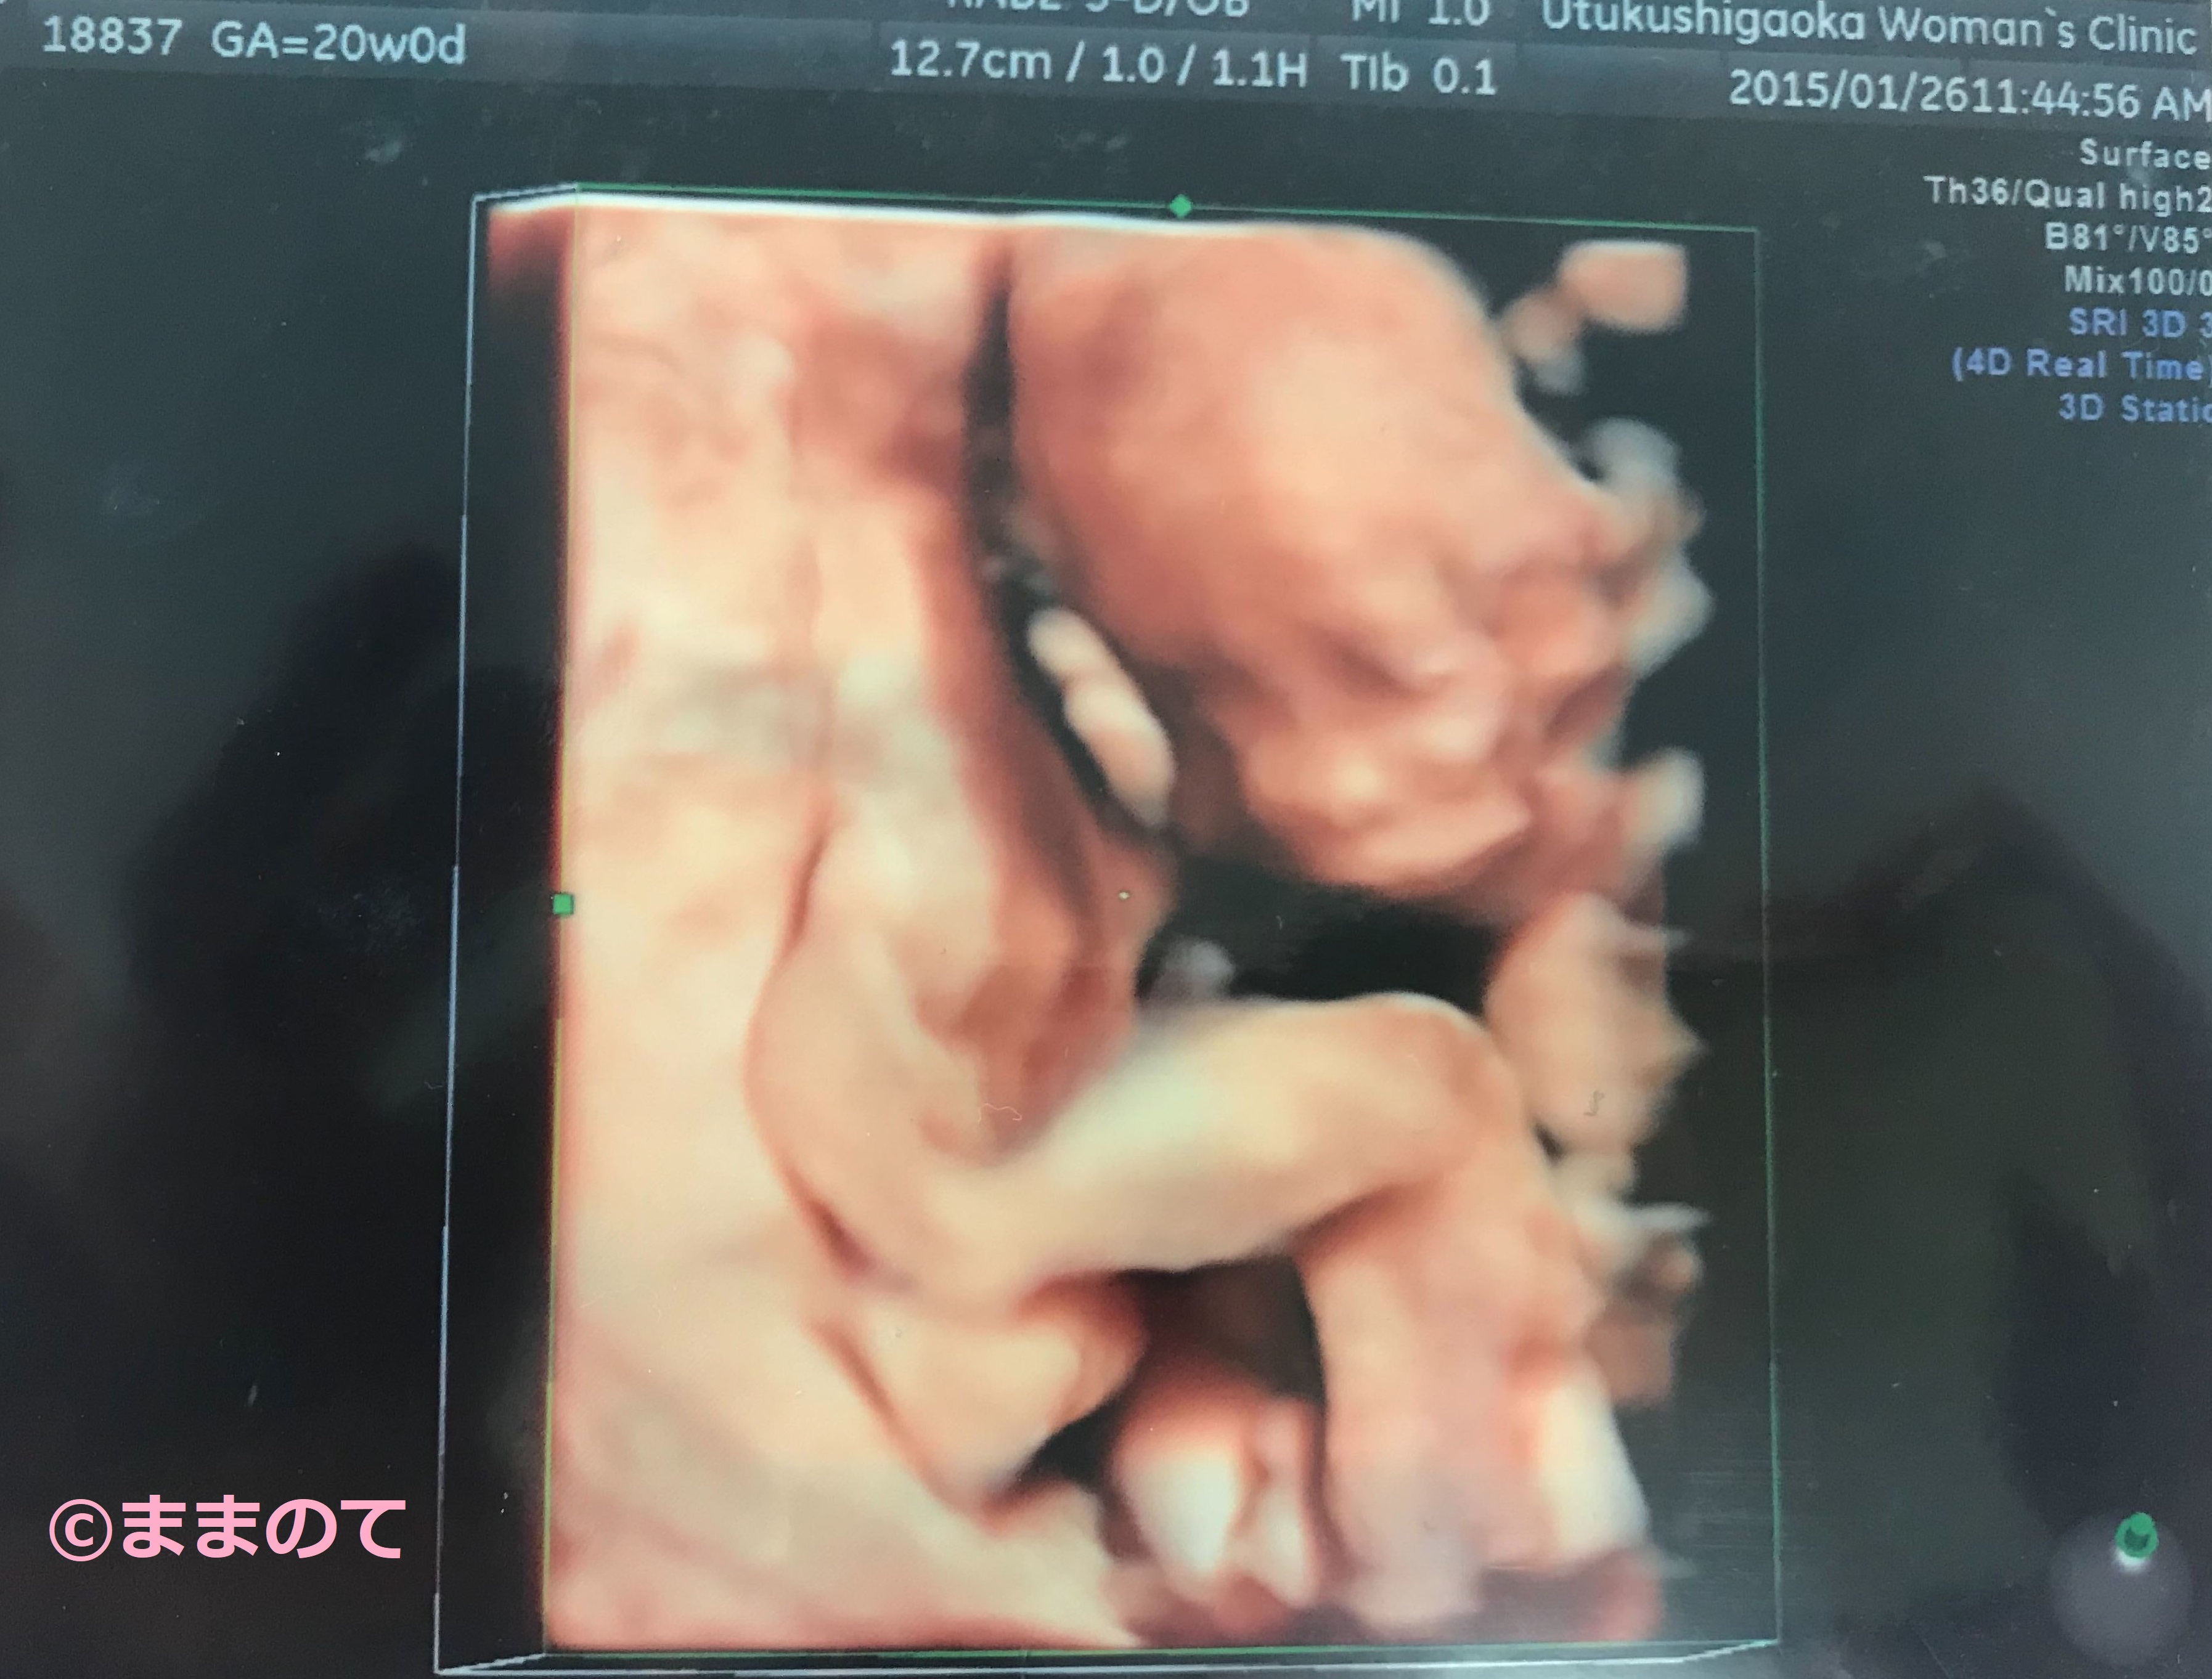

妊娠20週の赤ちゃんのエコー画像

妊娠20週の赤ちゃんは、表情がはっきりとわかりやすくなるころです。まぶたや口、鼻などの顔のパーツもエコー写真で確認することができます。骨や筋肉なども、しっかりと成長しているのがわかるでしょう。上記の写真は4Dエコーの写真です。眠っているのがわかりますね。